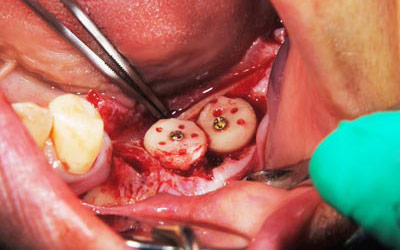

写真は、実際の手術の写真で、丸く採取された骨片が、スクリューで固定されています。

骨の移植手術後、移植した骨片が生着するのを数か月待って、インプラント埋入手術を行いました。写真はその時のもので、移植した骨が周囲の骨と一体化して、しっかりと骨が増えているのが分かります。